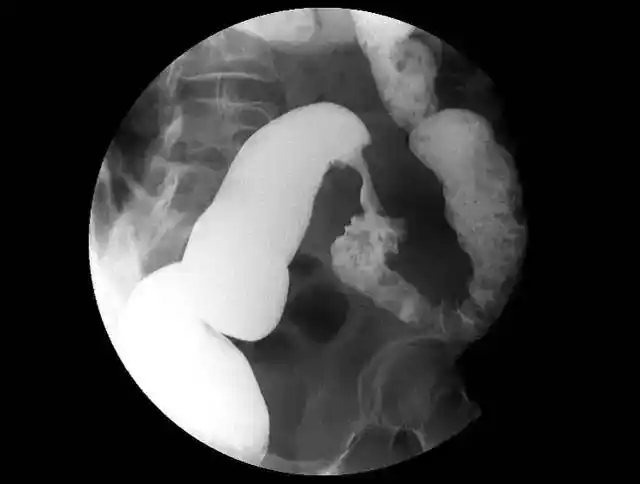

贲门失迟缓症的鸟嘴样改变

超声内镜经典病例鸟嘴征

"鸟嘴征"≠贲门失弛缓,还可能是这些恶性肿瘤,不要误诊了 | 经典eus